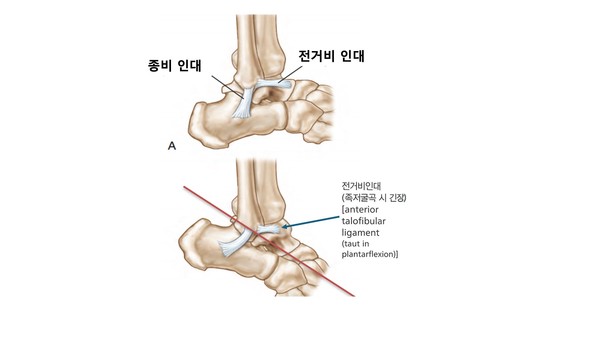

전거비 인대(anterior talofibular ligament)는 발목의 바깥쪽에 존재하는 가장 중요한 3개의 인대(전거비인대, 후거비인대, 종비인대) 중 하나입니다.

3가지 인대 중에서 가장 많이 손상 받는 인대가 바로 전거비 인대인데요, 그 이유 중 하나는 농구 중 발생하는 발목 손상의 매커니즘 때문입니다.

내번 손상을 당하게 되면 외측에 있는 발목 인대 3가지가 모두 손상 받을 수 있는데요, 손상 받을 당시의 발의 자세 또한 손상의 정도를 결정하는데 중요합니다.

많은 경우에서 발을 바닥에 디디는 과정에서 상대방의 발을 밟아 다치게 되는 데 이때 발목이 펴지는 (족저굴곡) 상태에서 발생합니다.

해부학적으로 발목을 펴게 되면 (족저굴곡) 외측 발목 인대 중에서 “전거비인대”가 가장 길이가 늘어가는 긴장 상태가 됩니다. 이 상태에서 내번 손상으로 발목을 접지르게 되면 전거비 인대가 파열될 가능성이 매우 높아지는 겁니다. 이러한 이유로 농구에서 전거비인대 손상은 발목 손상에서 가장 흔하게 발생합니다.